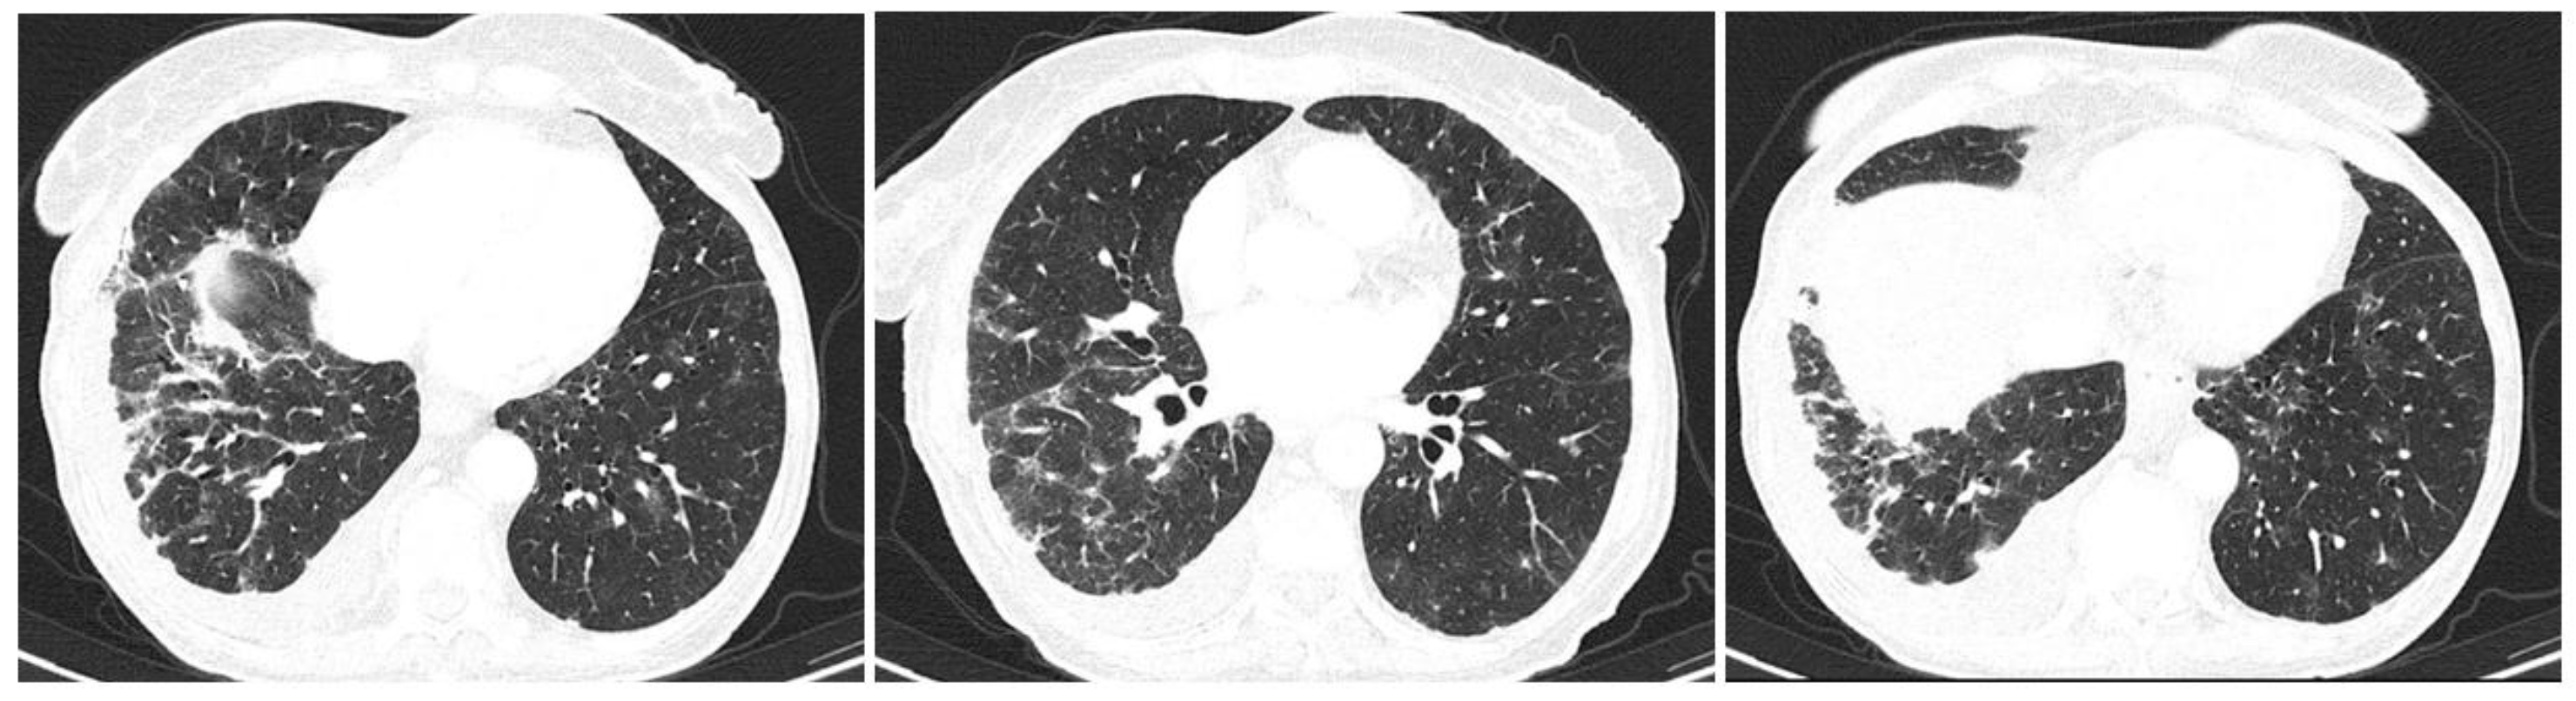

- Egashira, R. High-Resolution CT Findings of Myositis-Related Interstitial Lung Disease. Medicina 2021, 57, 692. [Google Scholar] [CrossRef]